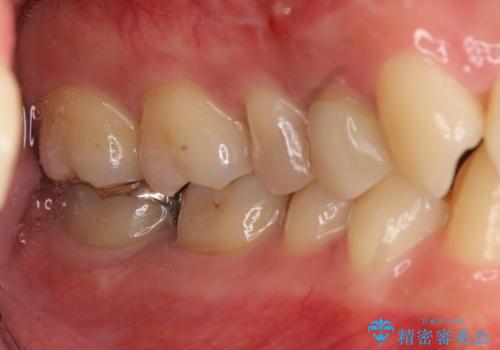

術後は瘻孔、圧痛、打診痛も消失し、根尖病変の縮小もみられました。経過良好です。

セラミック治療の注意事項(リスク・副作用など)

- 天然歯を削ります

- 硬い素材は天然歯を傷つけてしまう場合があります

- かみ合わせや歯ぎしりが強すぎる方はセラミックが割れてしまう可能性があります